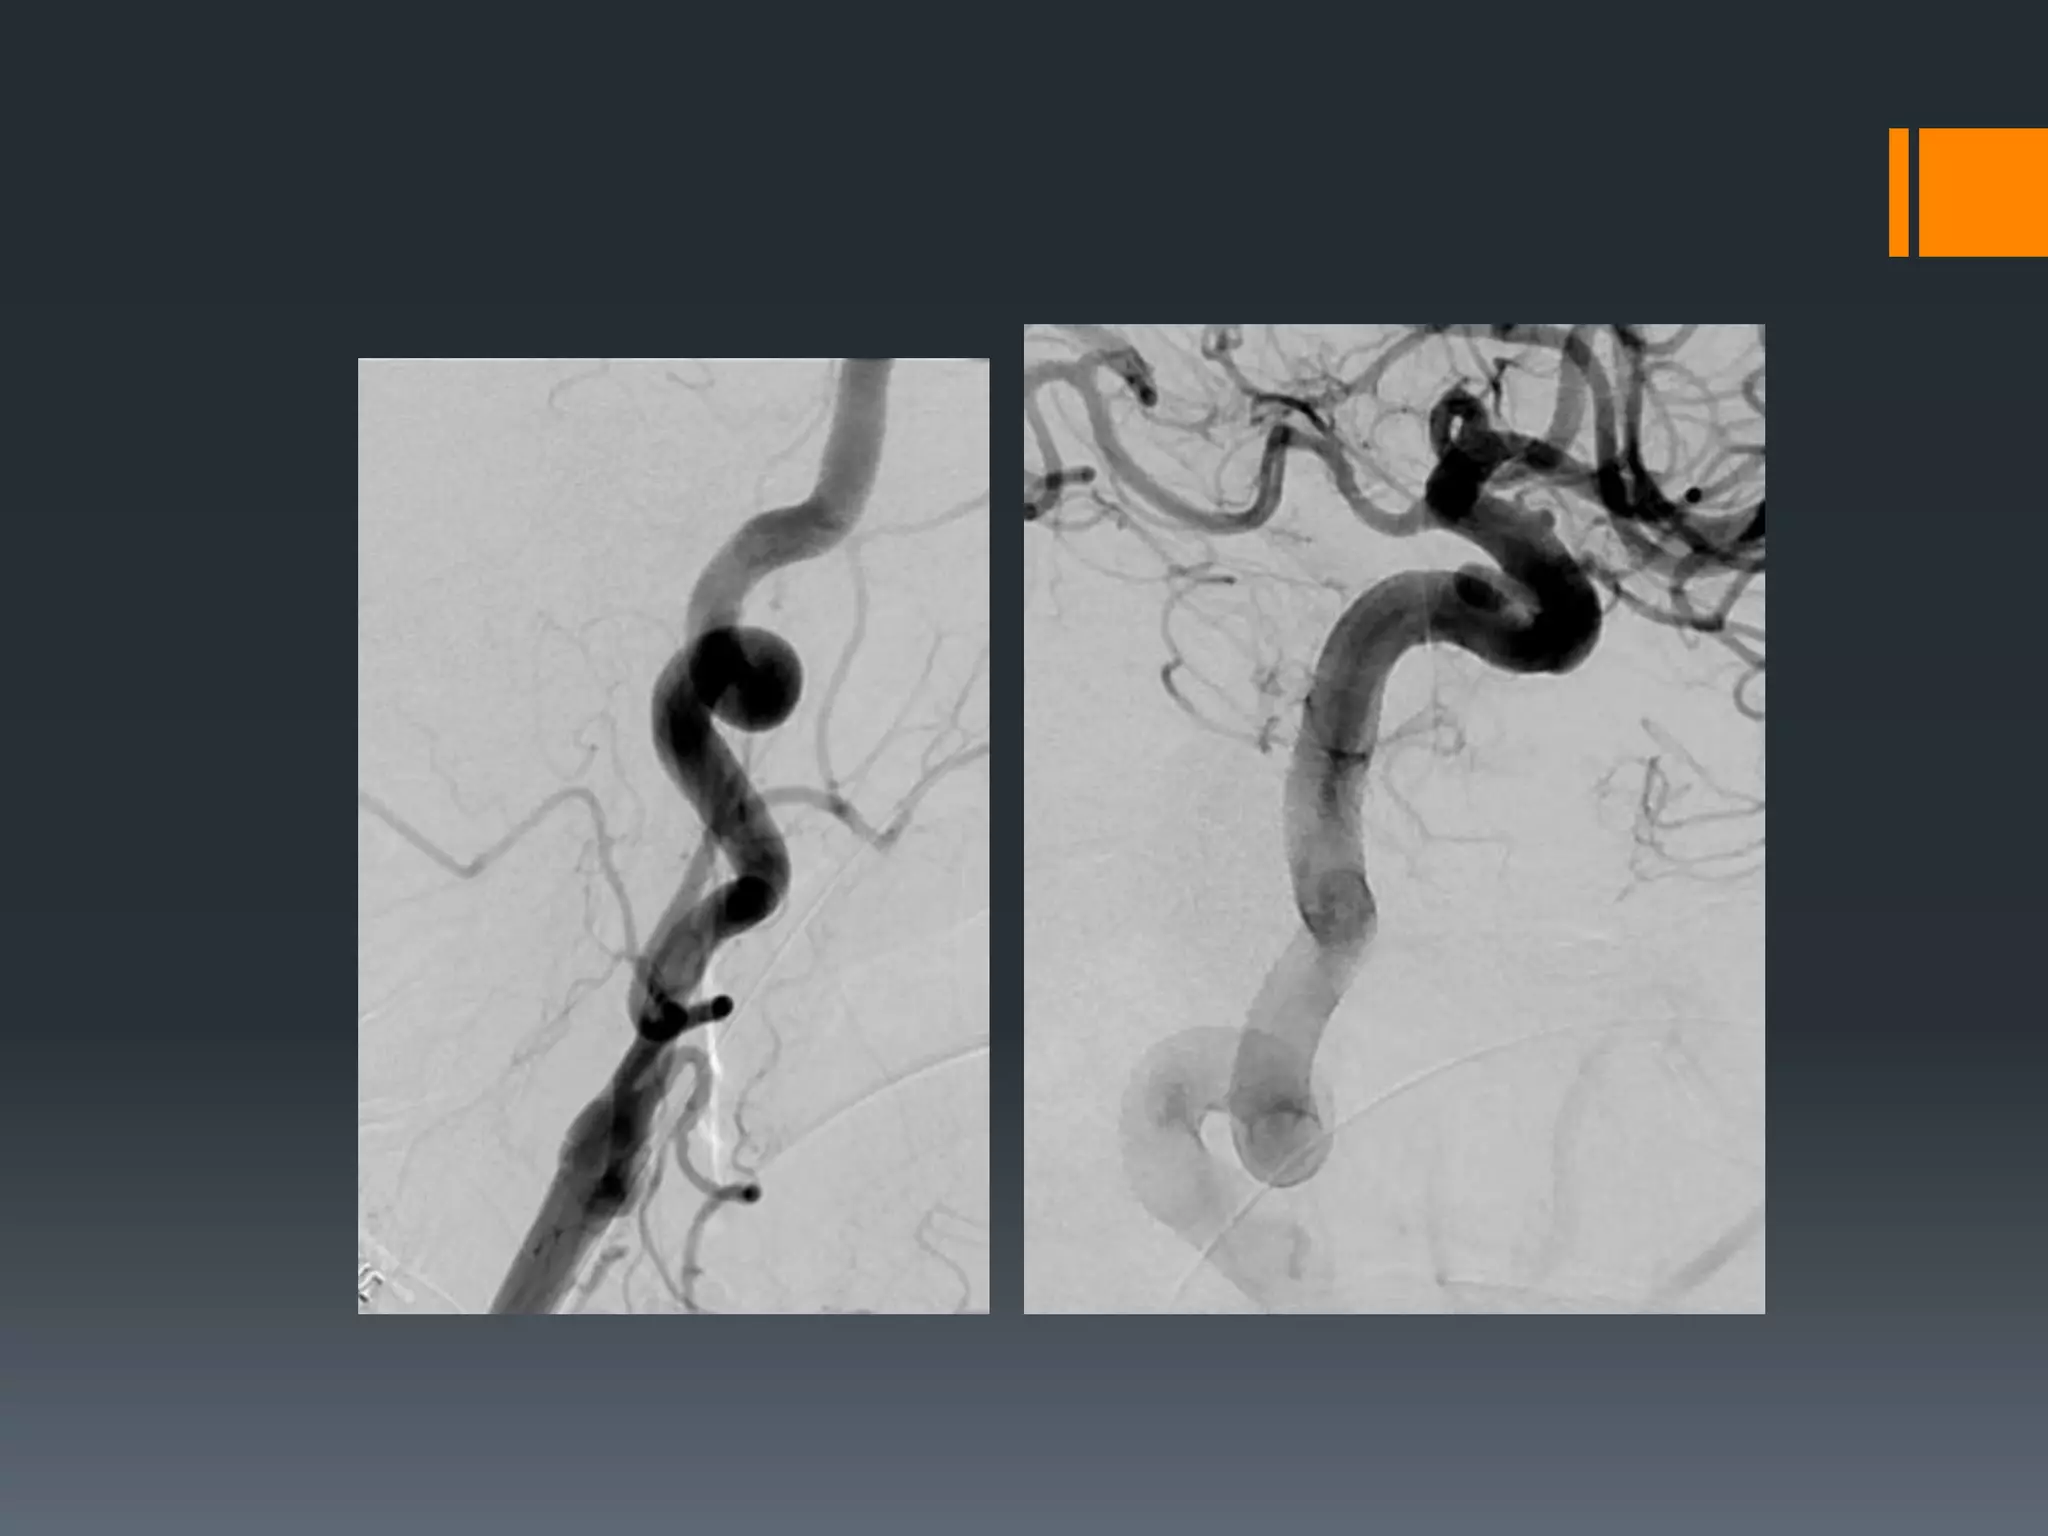

This document discusses tricks and techniques for difficult cannulations during neurointerventional procedures. It outlines strategies for accessing the aortic arch, internal carotid artery (ICA), and areas distal to aneurysms. Long sheaths, distal access catheters, and co-axial techniques are presented as options that have improved cannulation success. Guidance on sheath and catheter selection is provided for different vessel paths. The importance of catheter placement as high as possible in the ICA is emphasized. Reverse curve cannulations are also mentioned. Overall, the document stresses that careful cannulation is critical for procedural success and different strategies may be needed depending on the vessel target.